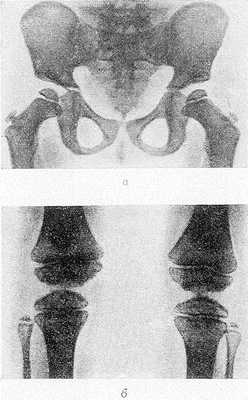

Рис. Рентгенограммы таза (а) и коленных суставов (б) ребенка с болезнью Фэрбанка (прямая проекция): эпифизы бедренных и берцовых костей уменьшены в размерах, высота их снижена, суставные поверхности неровные.

Рентгенол. картина Ф. б. весьма характерна. Типичные изменения чаще наблюдаются в тазобедренных и коленных суставах. Эпифизы костей уменьшены в размерах, особенно в поперечнике; их основание заметно короче эпифизарного хряща (рис., а); дистальные концы диафизов бедренных костей уплощены, межмыщелковая ямка неглубокая, плоская (рис., б).